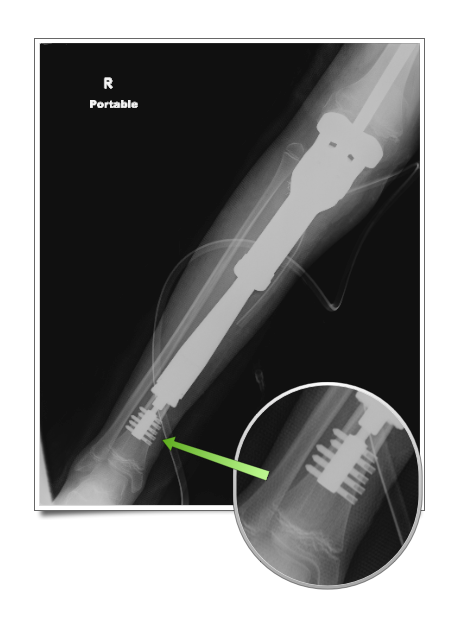

When surgery is performed for a bone sarcoma, the affected bone and some of the attached muscle is removed. After the tumor is removed, the missing bone needs to be replaced. In many cases this is done using a metal implant shaped like the missing bone. The detached muscles are re-attached to the implant or other nearby muscles, as needed.

Since many malignant tumors affect the ends of bones, it is common to have to replace a joint along with the bone. This is most common for the knee, hip and shoulder joints. In these cases, an implanted joint prosthesis ("endoprosthesis") is used to replace the missing bone and joint.

Same patient one year later, following distal femur resection & endoprosthetic reconstruction